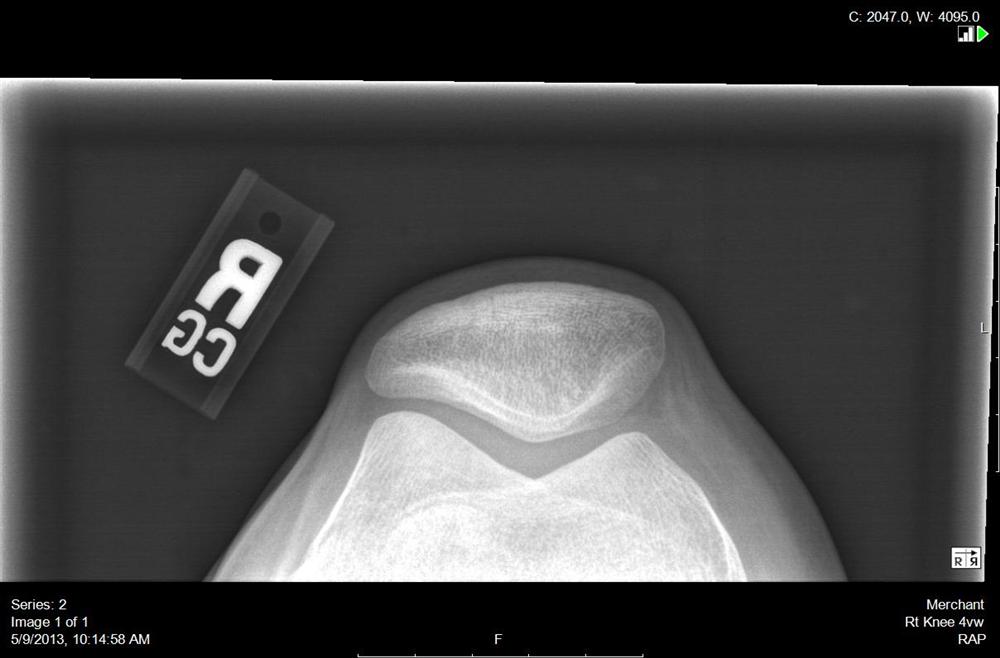

Radiographic Positioning Examples of the Knee Patella Views CE4RT Knee X Ray Merchant View Anteroposterior (ap), lateral, and axial (sunrise or merchant). Standard radiographic examination of the knee consists of three views: The knee series is a set of radiographs taken to investigate knee joint pathology, often in the context of trauma. 3.0 t mri has accuracy, sensitivity, and specificity of >90% for detecting medial and lateral meniscus tears. Horizontal ray (lateromedial) = supine. Knee X Ray Merchant View.

Axial (Merchant) view of the knees demonstrating normal Openi Knee X Ray Merchant View Anteroposterior (ap), lateral, and axial (sunrise or merchant). The knee series is a set of radiographs taken to investigate knee joint pathology, often in the context of trauma. Standard radiographic examination of the knee consists of three views: 3.0 t mri has accuracy, sensitivity, and specificity of >90% for detecting medial and lateral meniscus tears. It usually comprises an ap. Knee X Ray Merchant View.